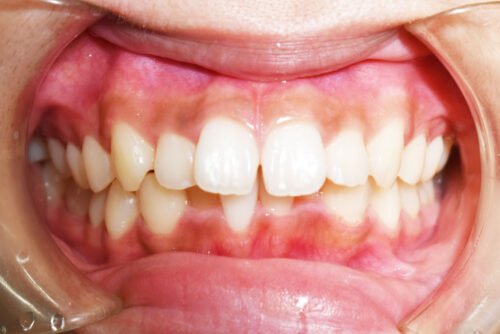

ワイヤー矯正治療7か月後です。

本症例も

矯正治療の精密検査後

非抜歯矯正治療計画を立案しました。

本症例のように

歯科矯正用アンカースクリュー(デュアル・トップオートスクリュー)を利用し

下顎のオートローテーションを行うことで

歯を抜かない非抜歯矯正治療でも

E-lineを整えることができます。